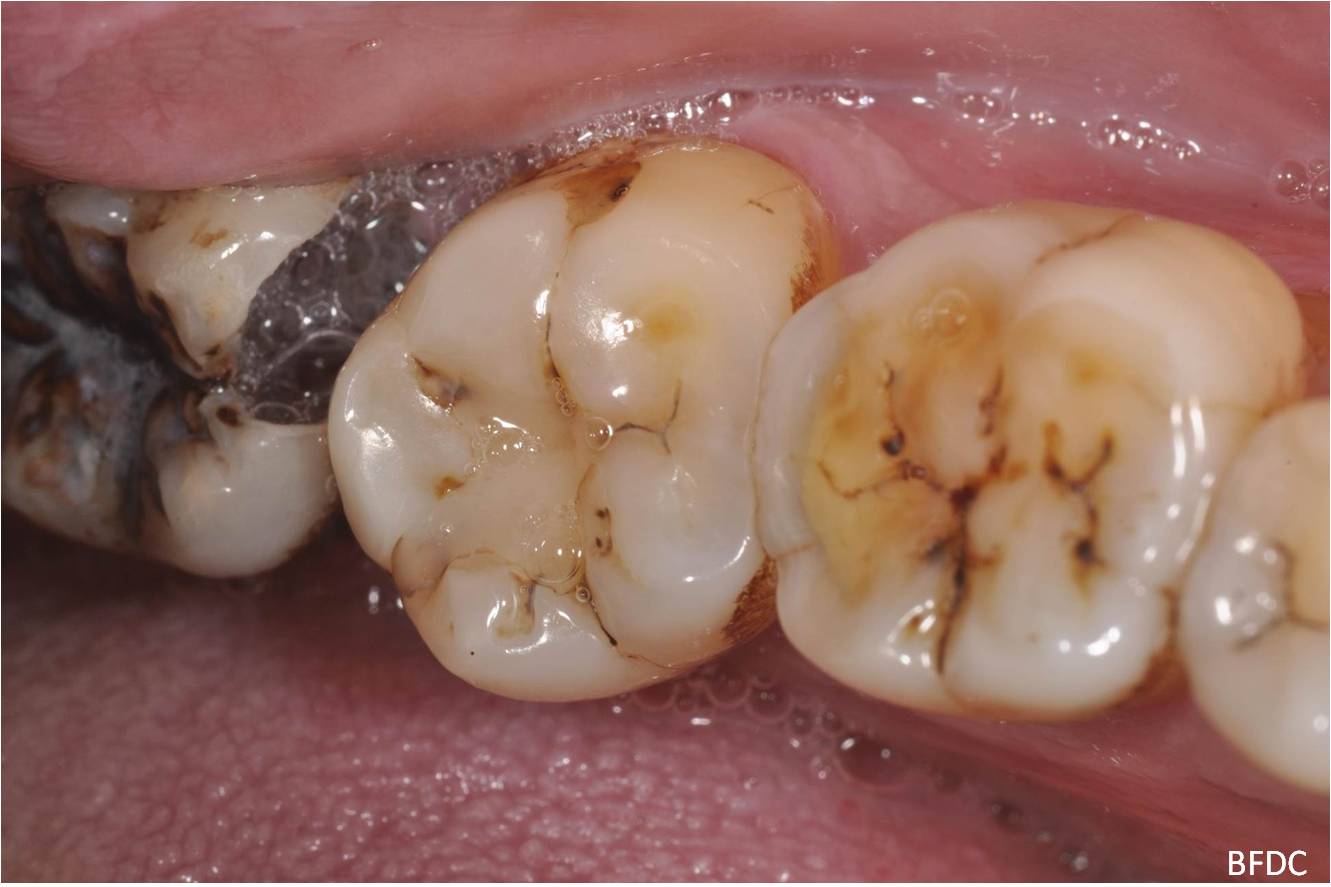

治療前,阻生齒塞食物,清潔不易,深度蛀牙

治療前,深度蛀牙